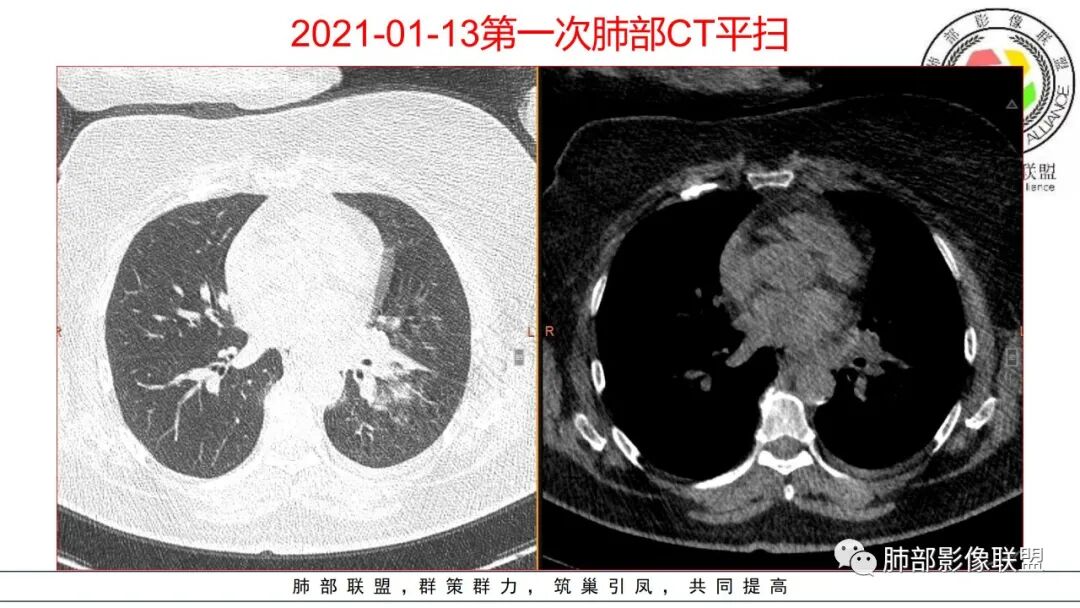

老年患者,糖尿病病史14年,不规律降糖治疗,血糖控制不佳,咳嗽、喘息两天就诊,查血常规白细胞轻度升高,CRP显著升高,首诊CT提示左下基底大片实变,边界不清,周围播散灶,短期复查病灶呈吸收好转趋势,并出现多发空洞,空洞形态不规则,病灶内未见气液平,考虑感染性病变:

1.老年女性,咳嗽喘息两天入院,没有发热记载。既往糖尿病控制不佳。临床CRP增高,首次实验室白细胞及中性轻度增高。

2.左肺下叶大范围实性密度影,散乱,边界不清,可见液化空洞,病变肺体积轻度增大。支气管相关(相应支气管闭塞)。